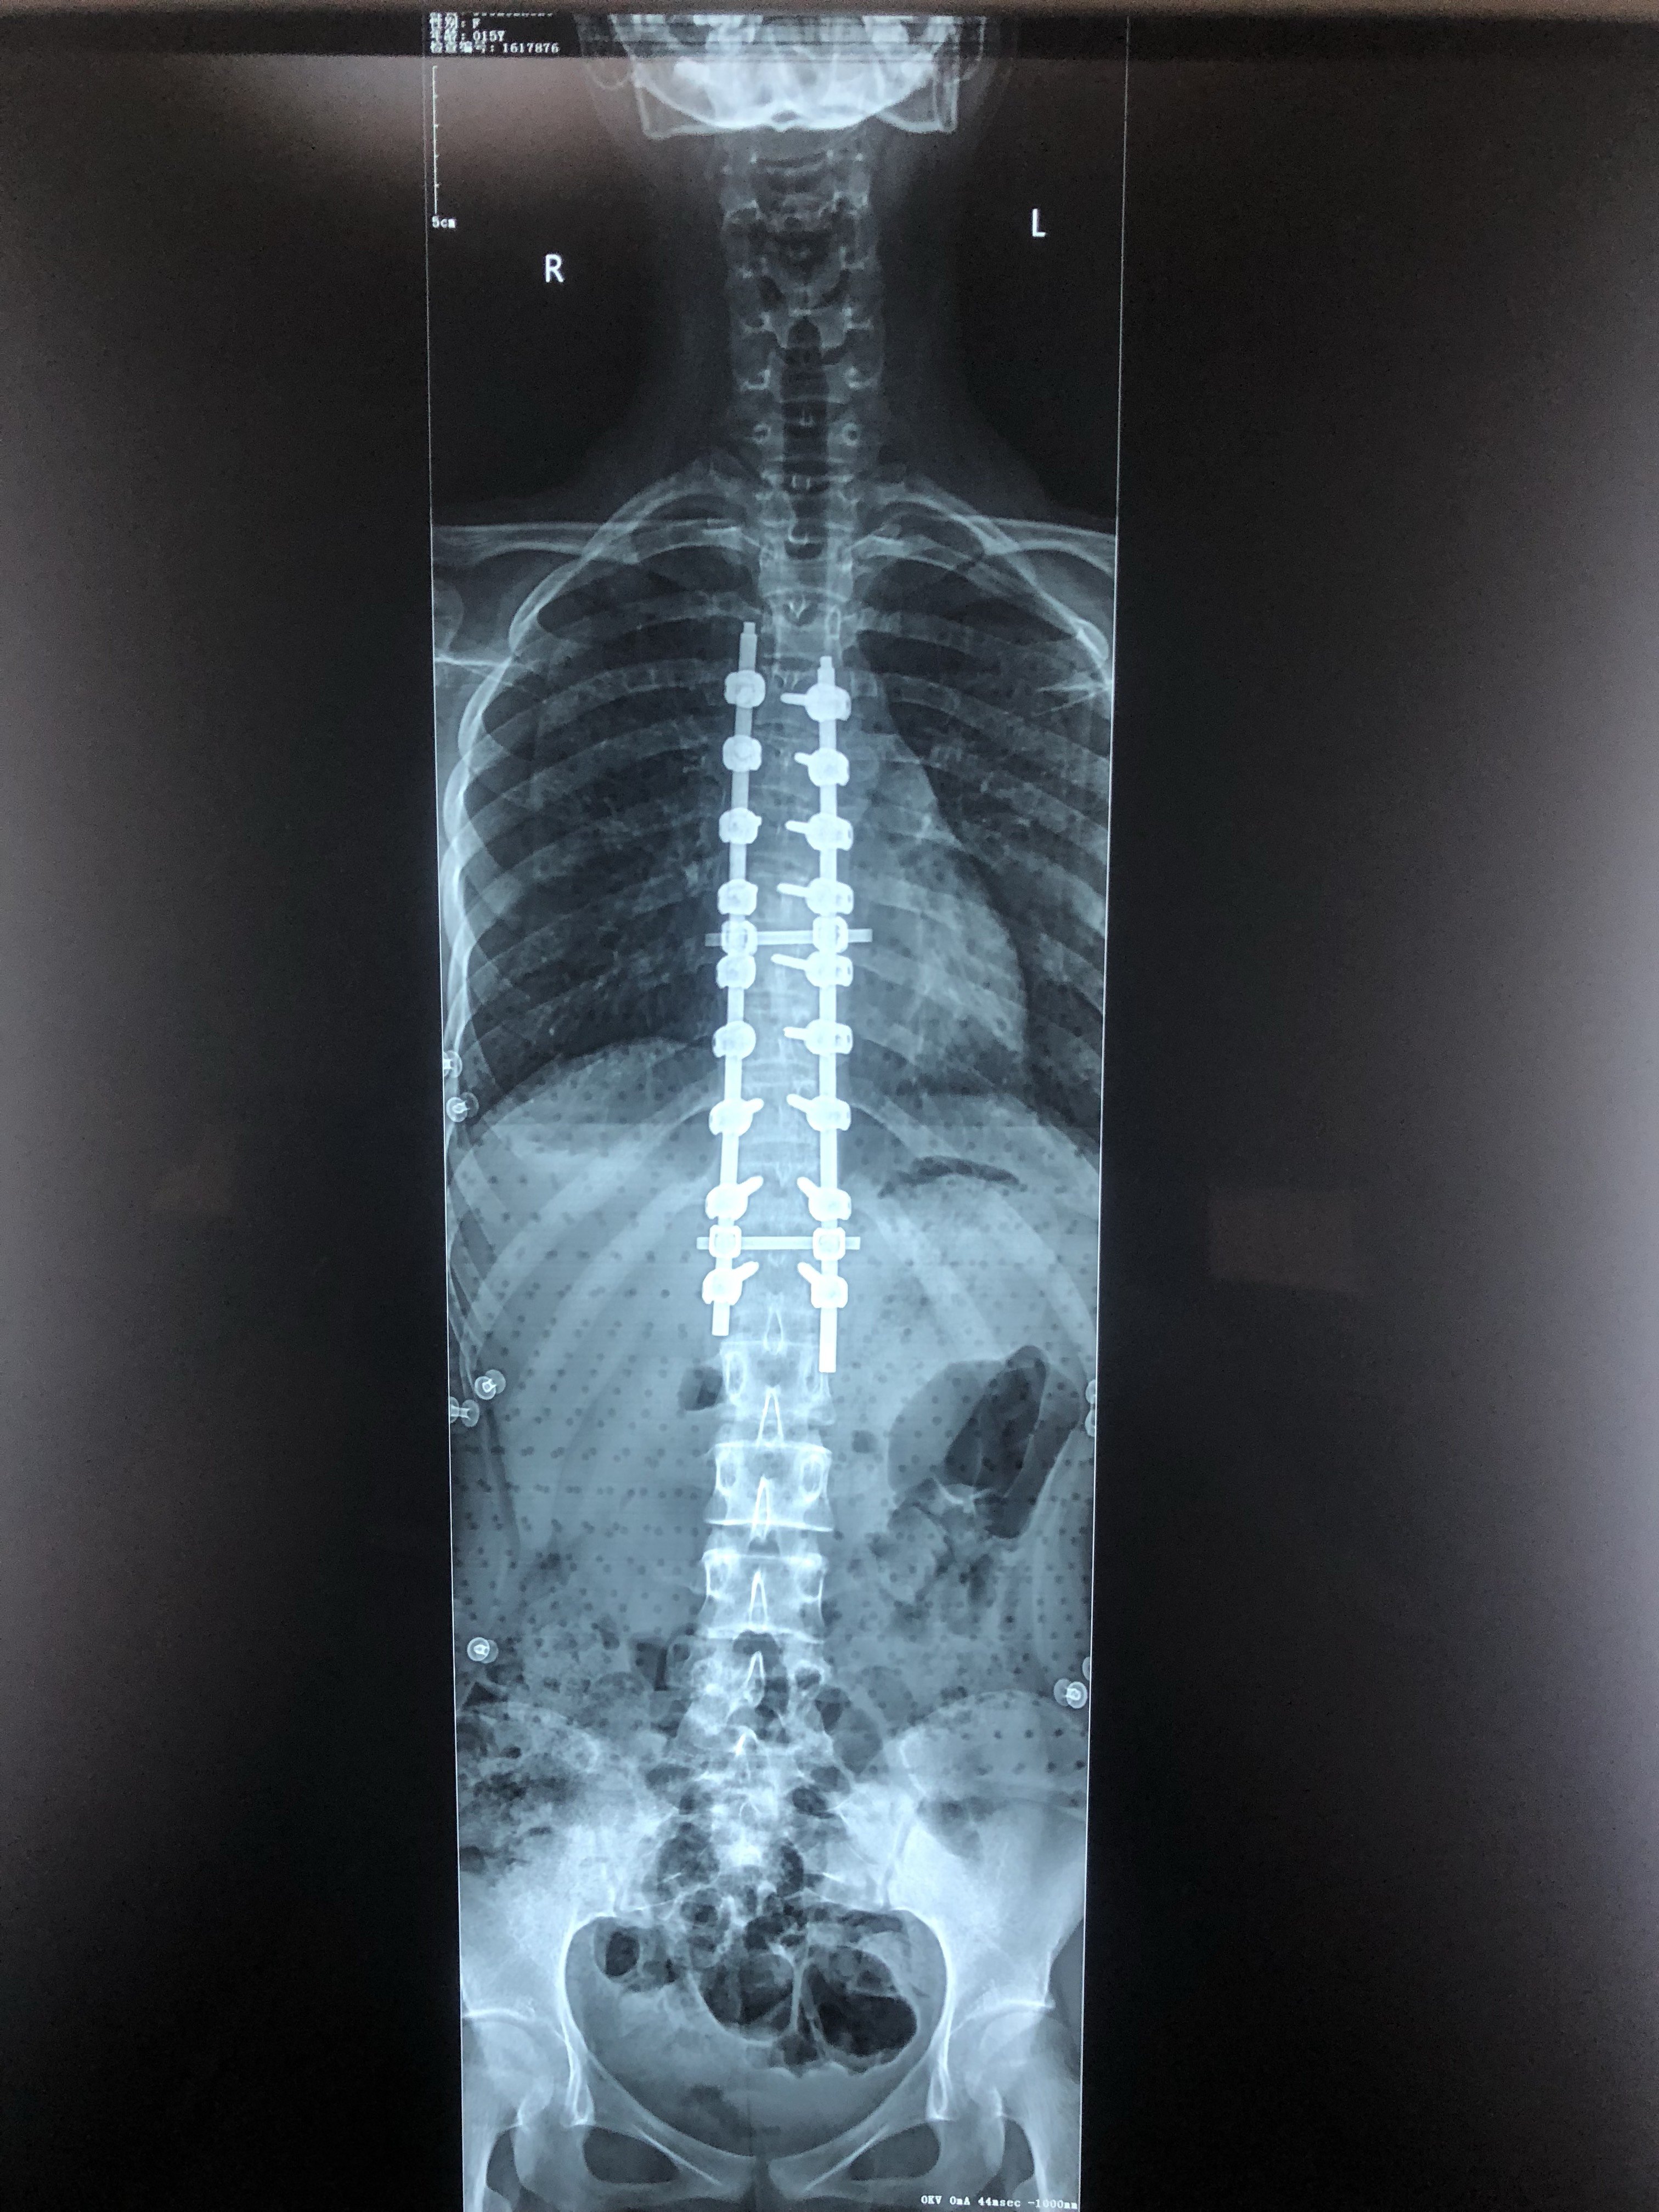

病情描述(主要症状、发病时间):我在8岁的时候父母发现我的脊柱开始变化医生诊断说是先天性脊柱侧弯17岁那年医生说可能有70多度曾经治疗情况和效果:我17岁那年坐着时

脊柱侧弯手术能彻底治愈么?